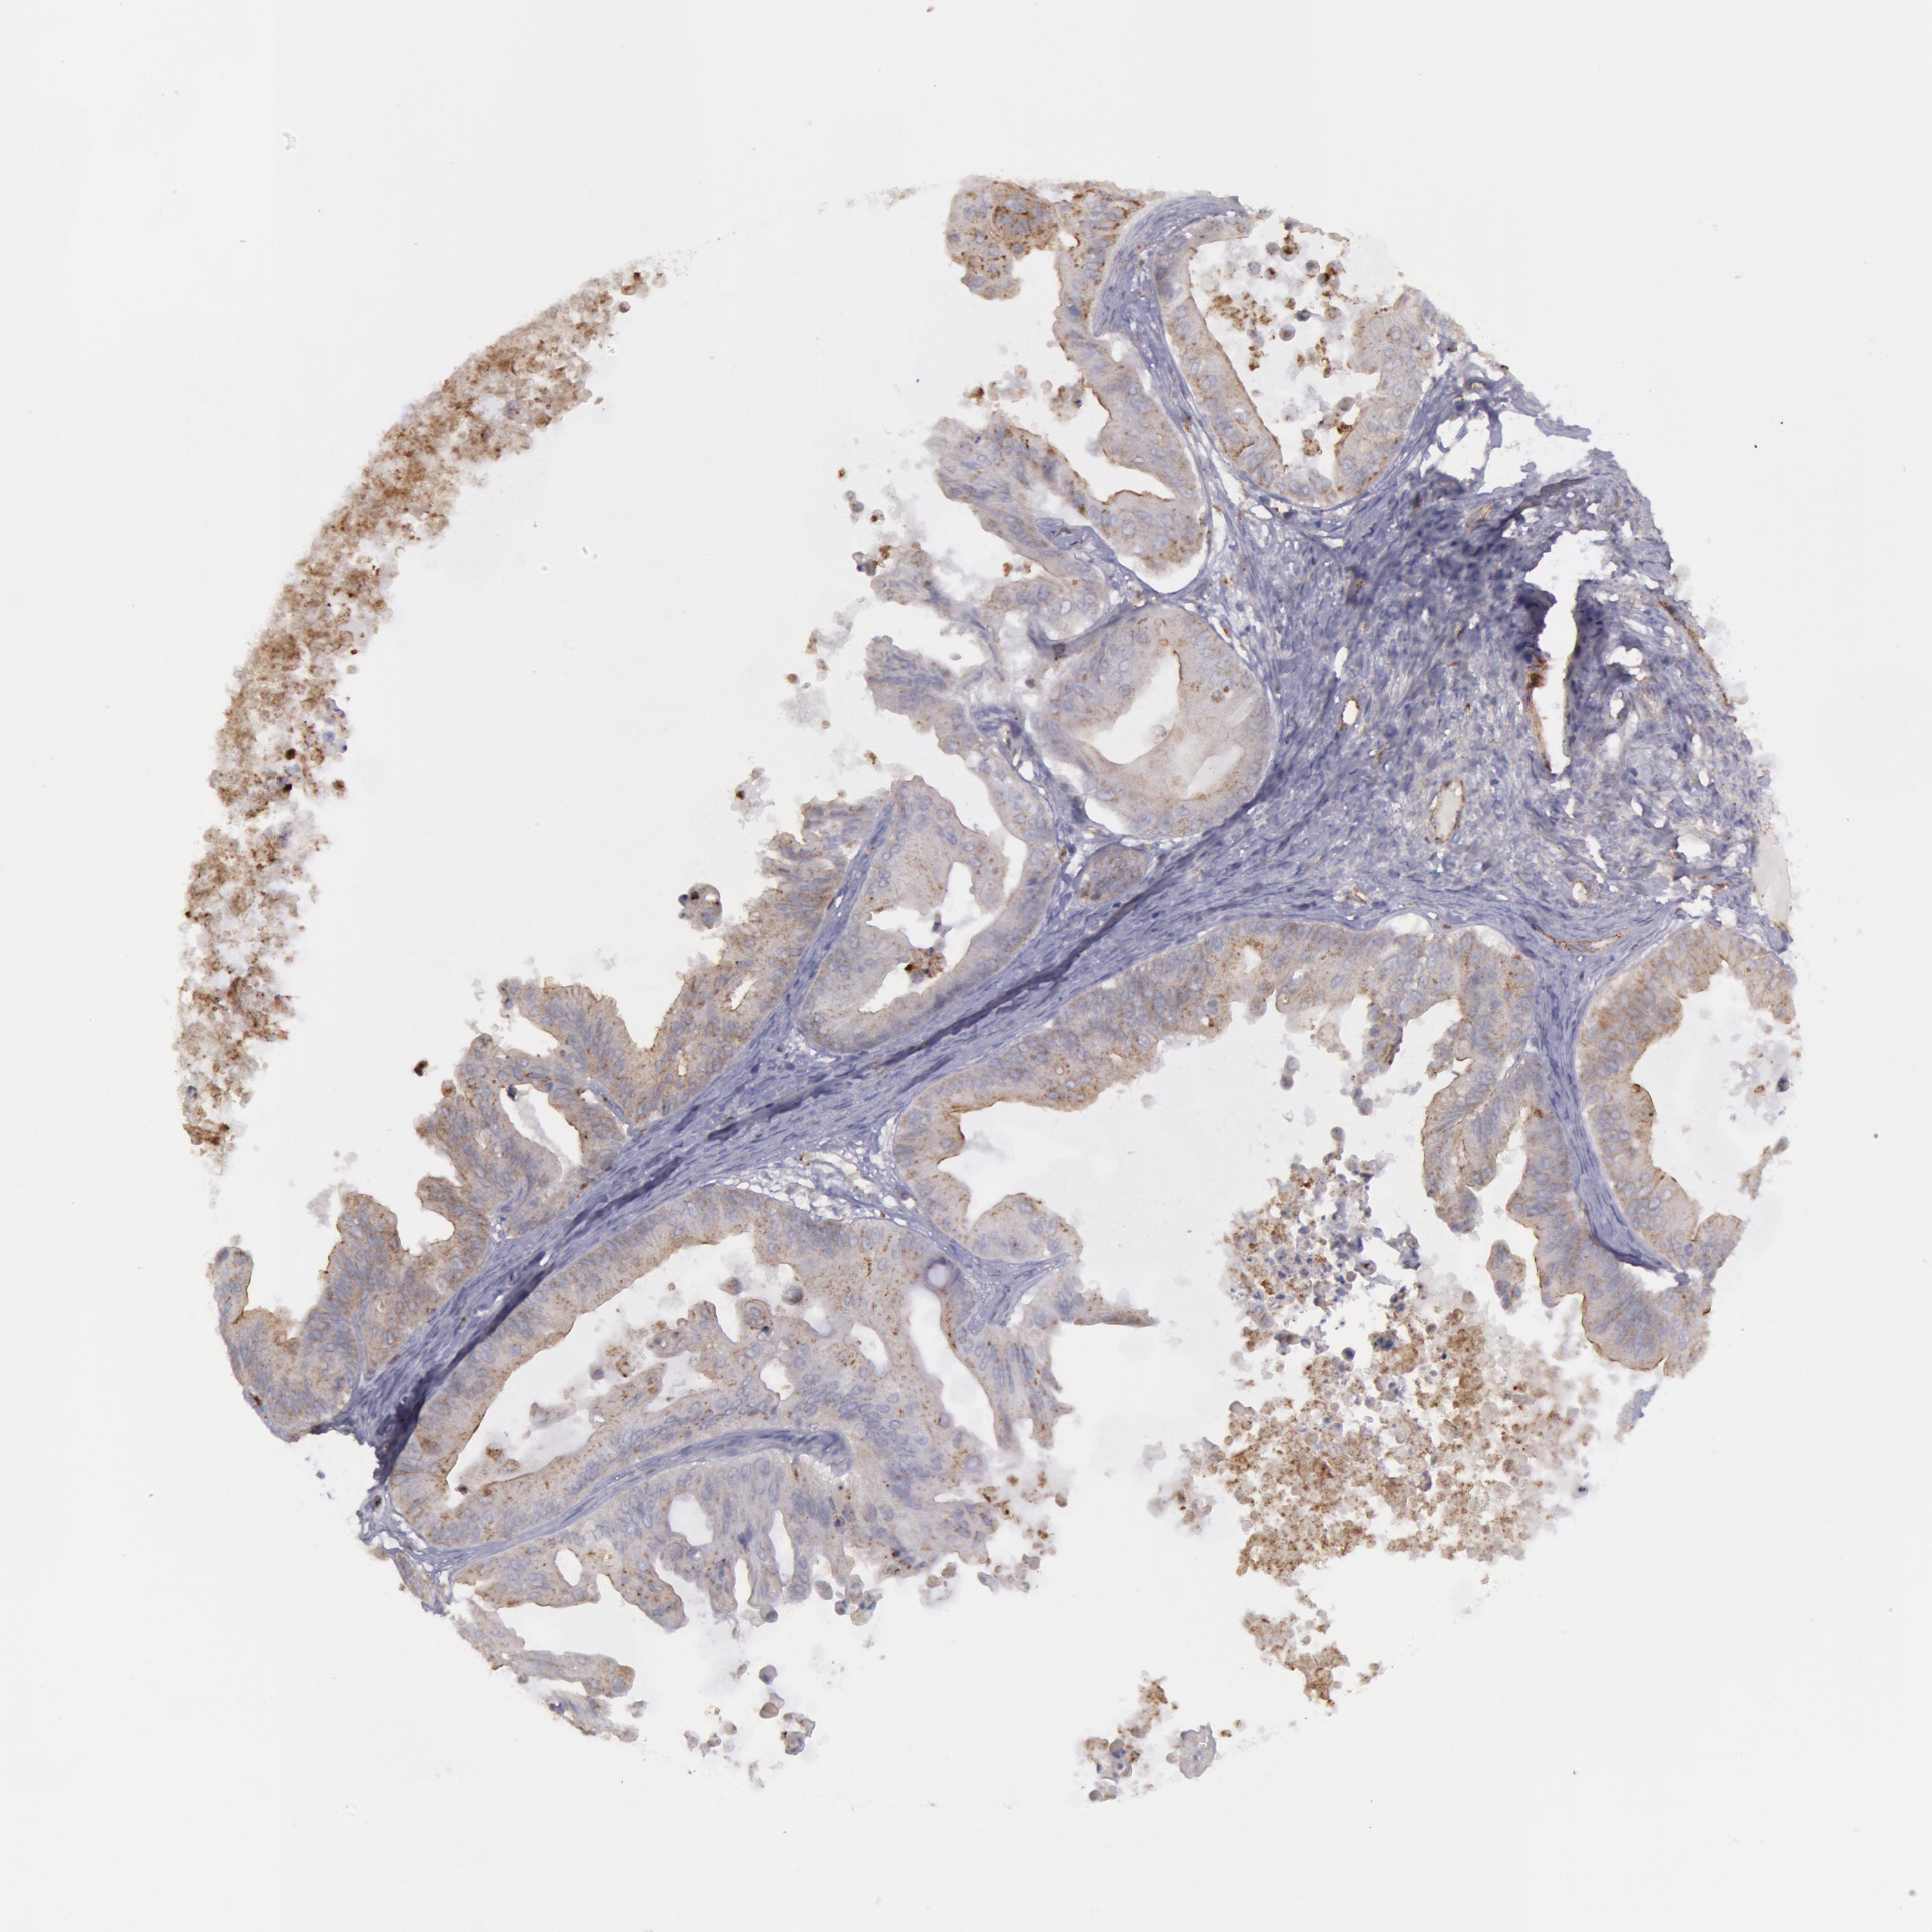

OVARIAN CANCER - Protein expressioni

A mouse-over function shows sample information and annotation data. Click on an image to view it in a full screen mode. Samples can be filtered based on level of antibody staining by selecting one or several of the following categories: high, medium, low and not detected. The assay and annotation is described here.

Note that samples used for immunohistochemistry by the Human Protein Atlas do not correspond to samples in the TCGA dataset.

Antibody stainingi

Antibody staining in the annotated cell types in the current human tissue is reported as not detected, low, medium, or high, based on conventional immunohistochemistry profiling in selected tissues. This score is based on the combination of the staining intensity and fraction of stained cells.

Each image is clickable and will lead to virtual microscopy that enables deeper exploration of all samples and also displays staining intensity scores, fraction scores and subcellular localization as well as patient and tissue information for each sample.

Antibody HPA001396

Antibody CAB004395

Cystadenocarcinoma, mucinous, NOS

Carcinoma, endometroid

Cystadenocarcinoma, serous, NOS

Carcinoma, NOS